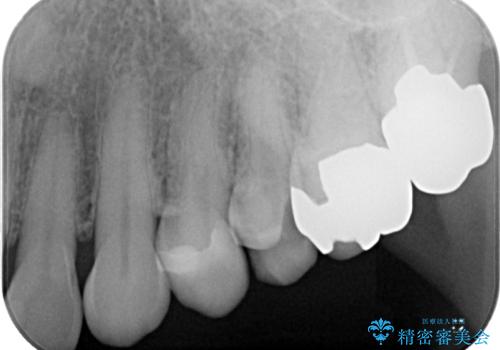

- 銀歯が取れたとのことで来院された患者様です。咬み合わせが強い方なので、ゴールドインレーでの治療をお勧めしましたが、ご本人の希望により審美性に優れたセラミックインレーでの治療を行っていくことにしました。

拡大鏡視野下で、保険のプラスチック、虫歯の除去を行い、セラミックインレーに適した形に整えました。

歯と歯の間の虫歯をコンポジットレジンや保険のメタルインレーで治すと段差ができたりして清掃性が悪くなるので、セラミックインレー修復やゴールドインレー修復などの適合の良い詰め物で治療することをオススメします。